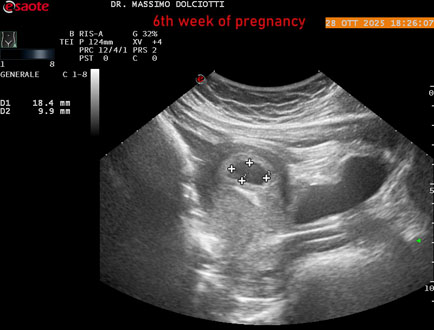

Sonda: Convex Multifrequenza 1-8 MHz

Età Paziente: F 35 anni

Motivazione dell'esame: amenorrea.

Commento all'esame: le immagini ed il video documentano in utero il sacco gestazionale, il sacco vitellino e presenza di embrione delle dimensioni di 4,7 mm (CRL), con iniziale attività cardiaca, documentata nel video.

Conclusioni: gravidanza alla 6° settimana di gestazione (pregnancy to the 6th week of gestation).